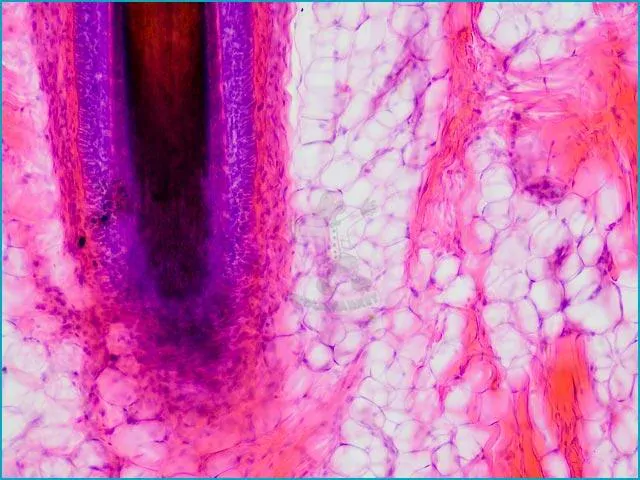

Mikroskopické preparáty – školní sada pro histologii č. 1, 23 ks